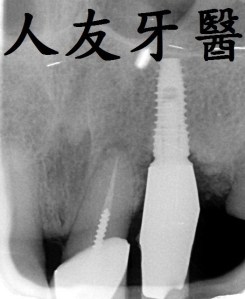

由上面那張照片我們可以清楚的看到不管是金屬牙套或內冠金屬外面燒瓷牙套都會釋放金屬離子 , 久了會造成牙齒與牙齦交接處黑黑的 , 因為模型有熱脹冷縮的關係 , 所以牙套本身也與自己的牙齒不是那麼密合 , 易從縫隙蛀進去 ; 而數位全鋯牙套 , 因牙套本身不含金屬材質所以不會有牙套釋放金屬離子的問題 , 牙齒與牙齦交接觸自然也不會黑黑的 , 因是數位取模 ,所以電腦設計精密度高 , 密合度自然也就比較好 .